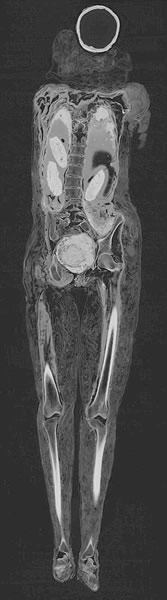

由于医院用的电脑断层扫描仪,这个木乃伊的性别最终得到确认。实际上,死者是名男子。

有人渴望知道尸体防腐者在这个木乃伊脸上画上胡须的原因。但直到20世纪60年代,有人用X射线检查这个木乃伊时,有关死者性别的疑问才被认真对待。现在由于医院用的电脑断层扫描仪,这个木乃伊的性别最终得到确认。实际上,死者是名男子。他的低领装是几捆布放在一起产生的结果。

相似填料还被用于鼓起他的大腿。学者们认为,两个区域可能被特意加入填料,因为这名男子很胖,尸体防腐者试图再现他生前的面貌。电脑断层扫描显示,他至少20岁,失去5颗牙齿,经历过几次令他痛苦不堪的牙龈脓疮。

这个木乃伊的“电子发掘”是伦敦中部大英博物馆20日举办的一个新展览的一部分。专家认为,这个木乃伊可追溯到公元2世纪,当时埃及在罗马统治下。专家用交互式可视化技术向观众展示了逐步打开这个木乃伊的过程。

公元前3500年到公元700年间,男人、女人和孩子生活在埃及和苏丹间尼罗河岸沿线。专家用史无前例的细节现在揭示了他们的生活和死亡。这些照片来自通常用于诊断肿瘤、骨折和心脏病的电脑断层扫描仪。